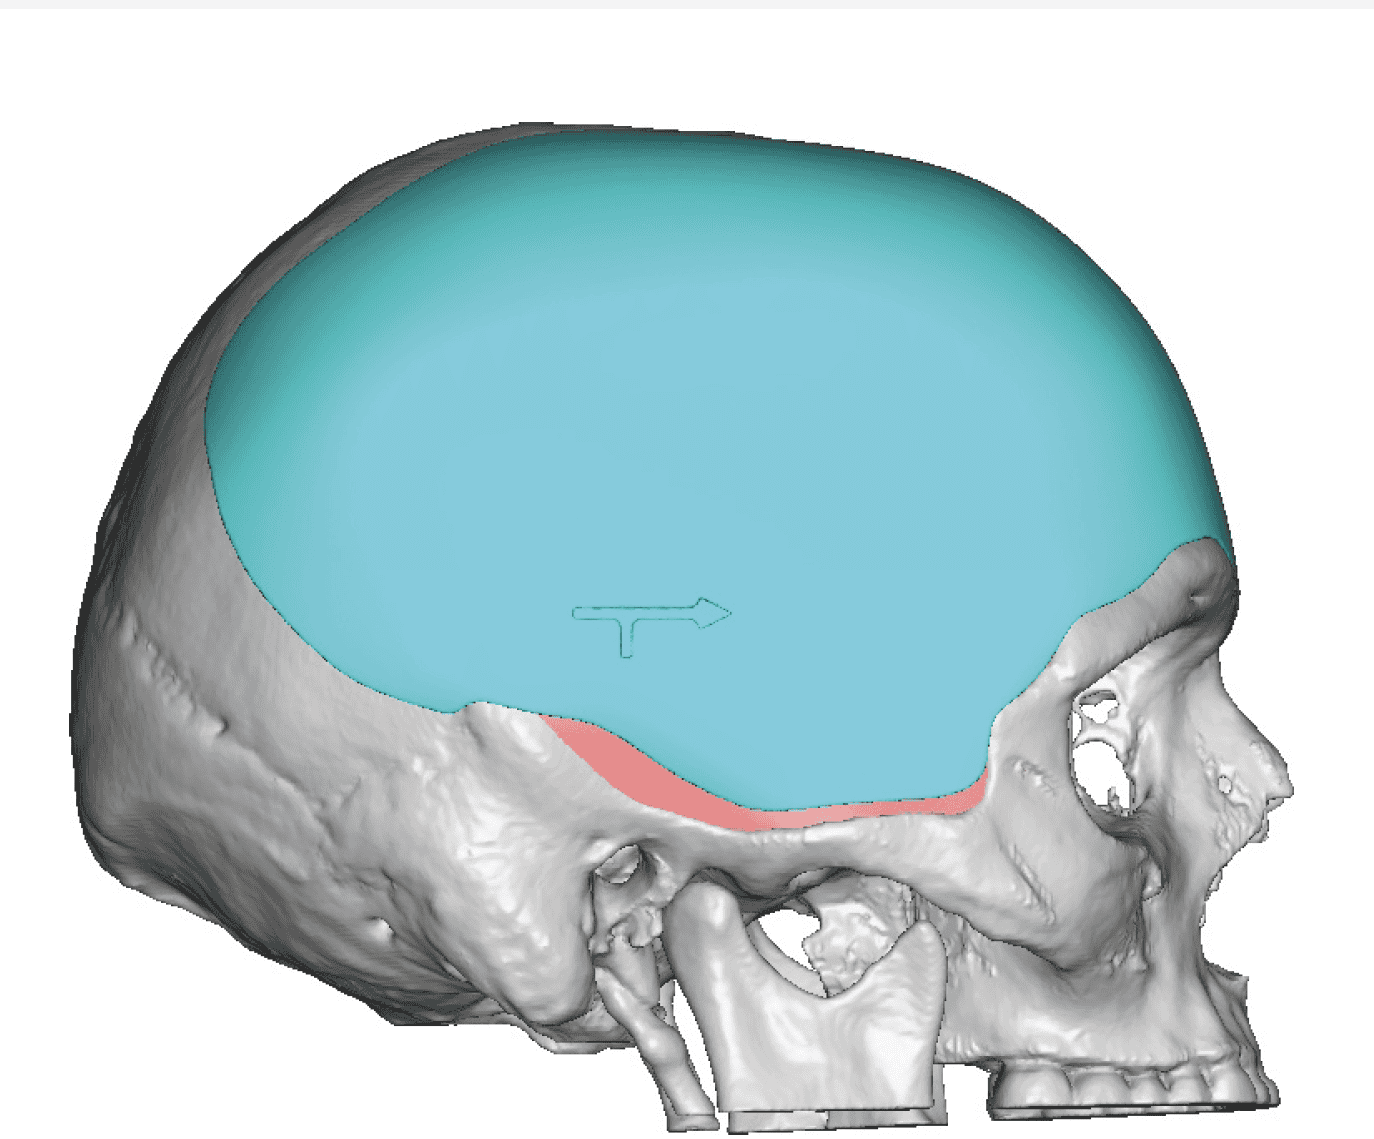

Patient 51

Desire for improved head shape that has a less peaked shape.

Placement of custom skull implant.

Desire for improved head shape that has a less peaked shape.

Placement of custom skull implant.